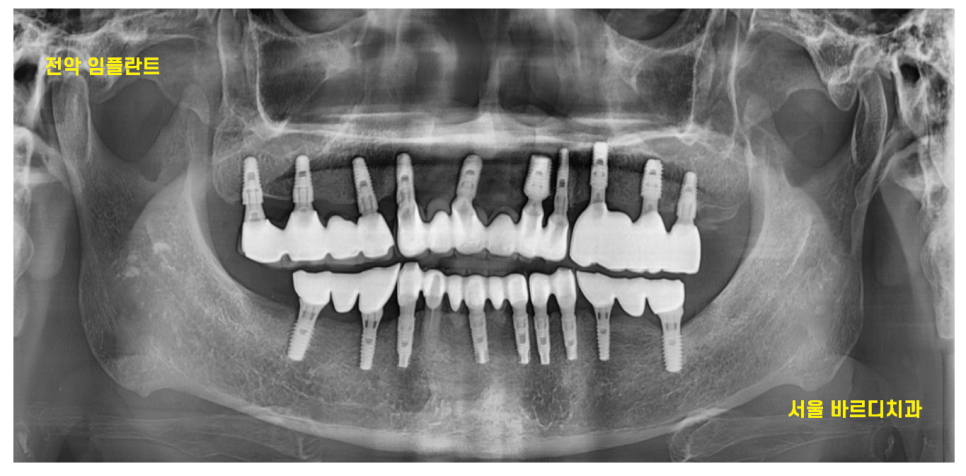

23.11.10

아이러니하게도ㅠㅠ

전악 임플란트 환자분들이 제일 잘 오십니다.

한번 치아를 잃어봤기 때문에

소중함을 알기 때문인데요.